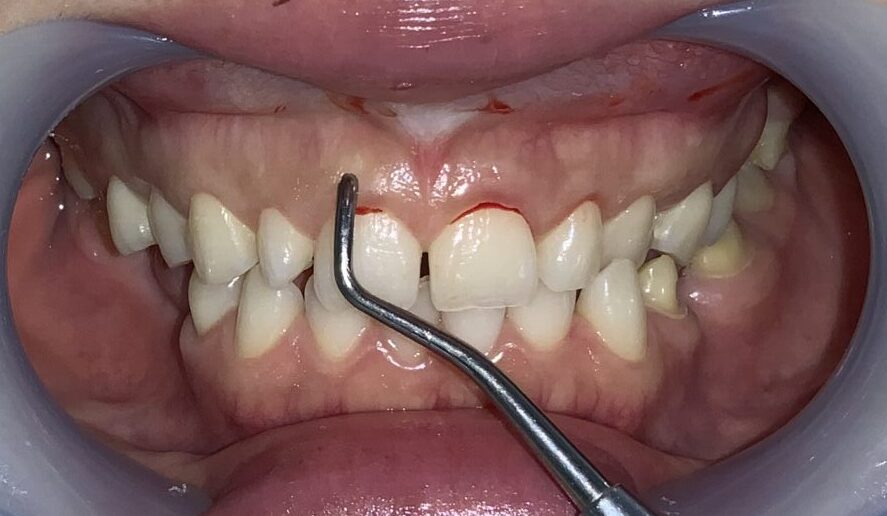

治療前の状態です。

歯の上にたくさんの歯ぐきが被っています。

前歯の歯ぐきの被り具合の検査をしています。

こちらの歯は歯ぐきの下の「歯槽骨」に尖っている部分がありそうです。

そして、歯ぐきは厚くて、歯ぐきの中に歯が埋まり込んでいる状態です。